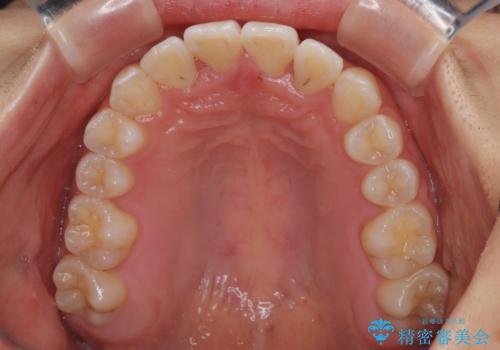

前歯のクロスバイト 裏側に隠れた歯をワイヤー装置で短期間治療

- 矯正装置

- メタルブラケット

- 上顎前歯のクロスバイトを気にして来院された患者様です。

ワイヤー矯正でもマウスピース矯正でも対応可能でしたが、マウスピースによる自己管理に一切の自信がないとのことで、ワイヤー装置にて矯正治療を行うこととしました。

装置の外見を気にしていましたが、短期間で治療を終えることができるだろうと伝えると、安価であるメタルブラケットを選択されました。

想定通り、1年強で綺麗に仕上げることができました。